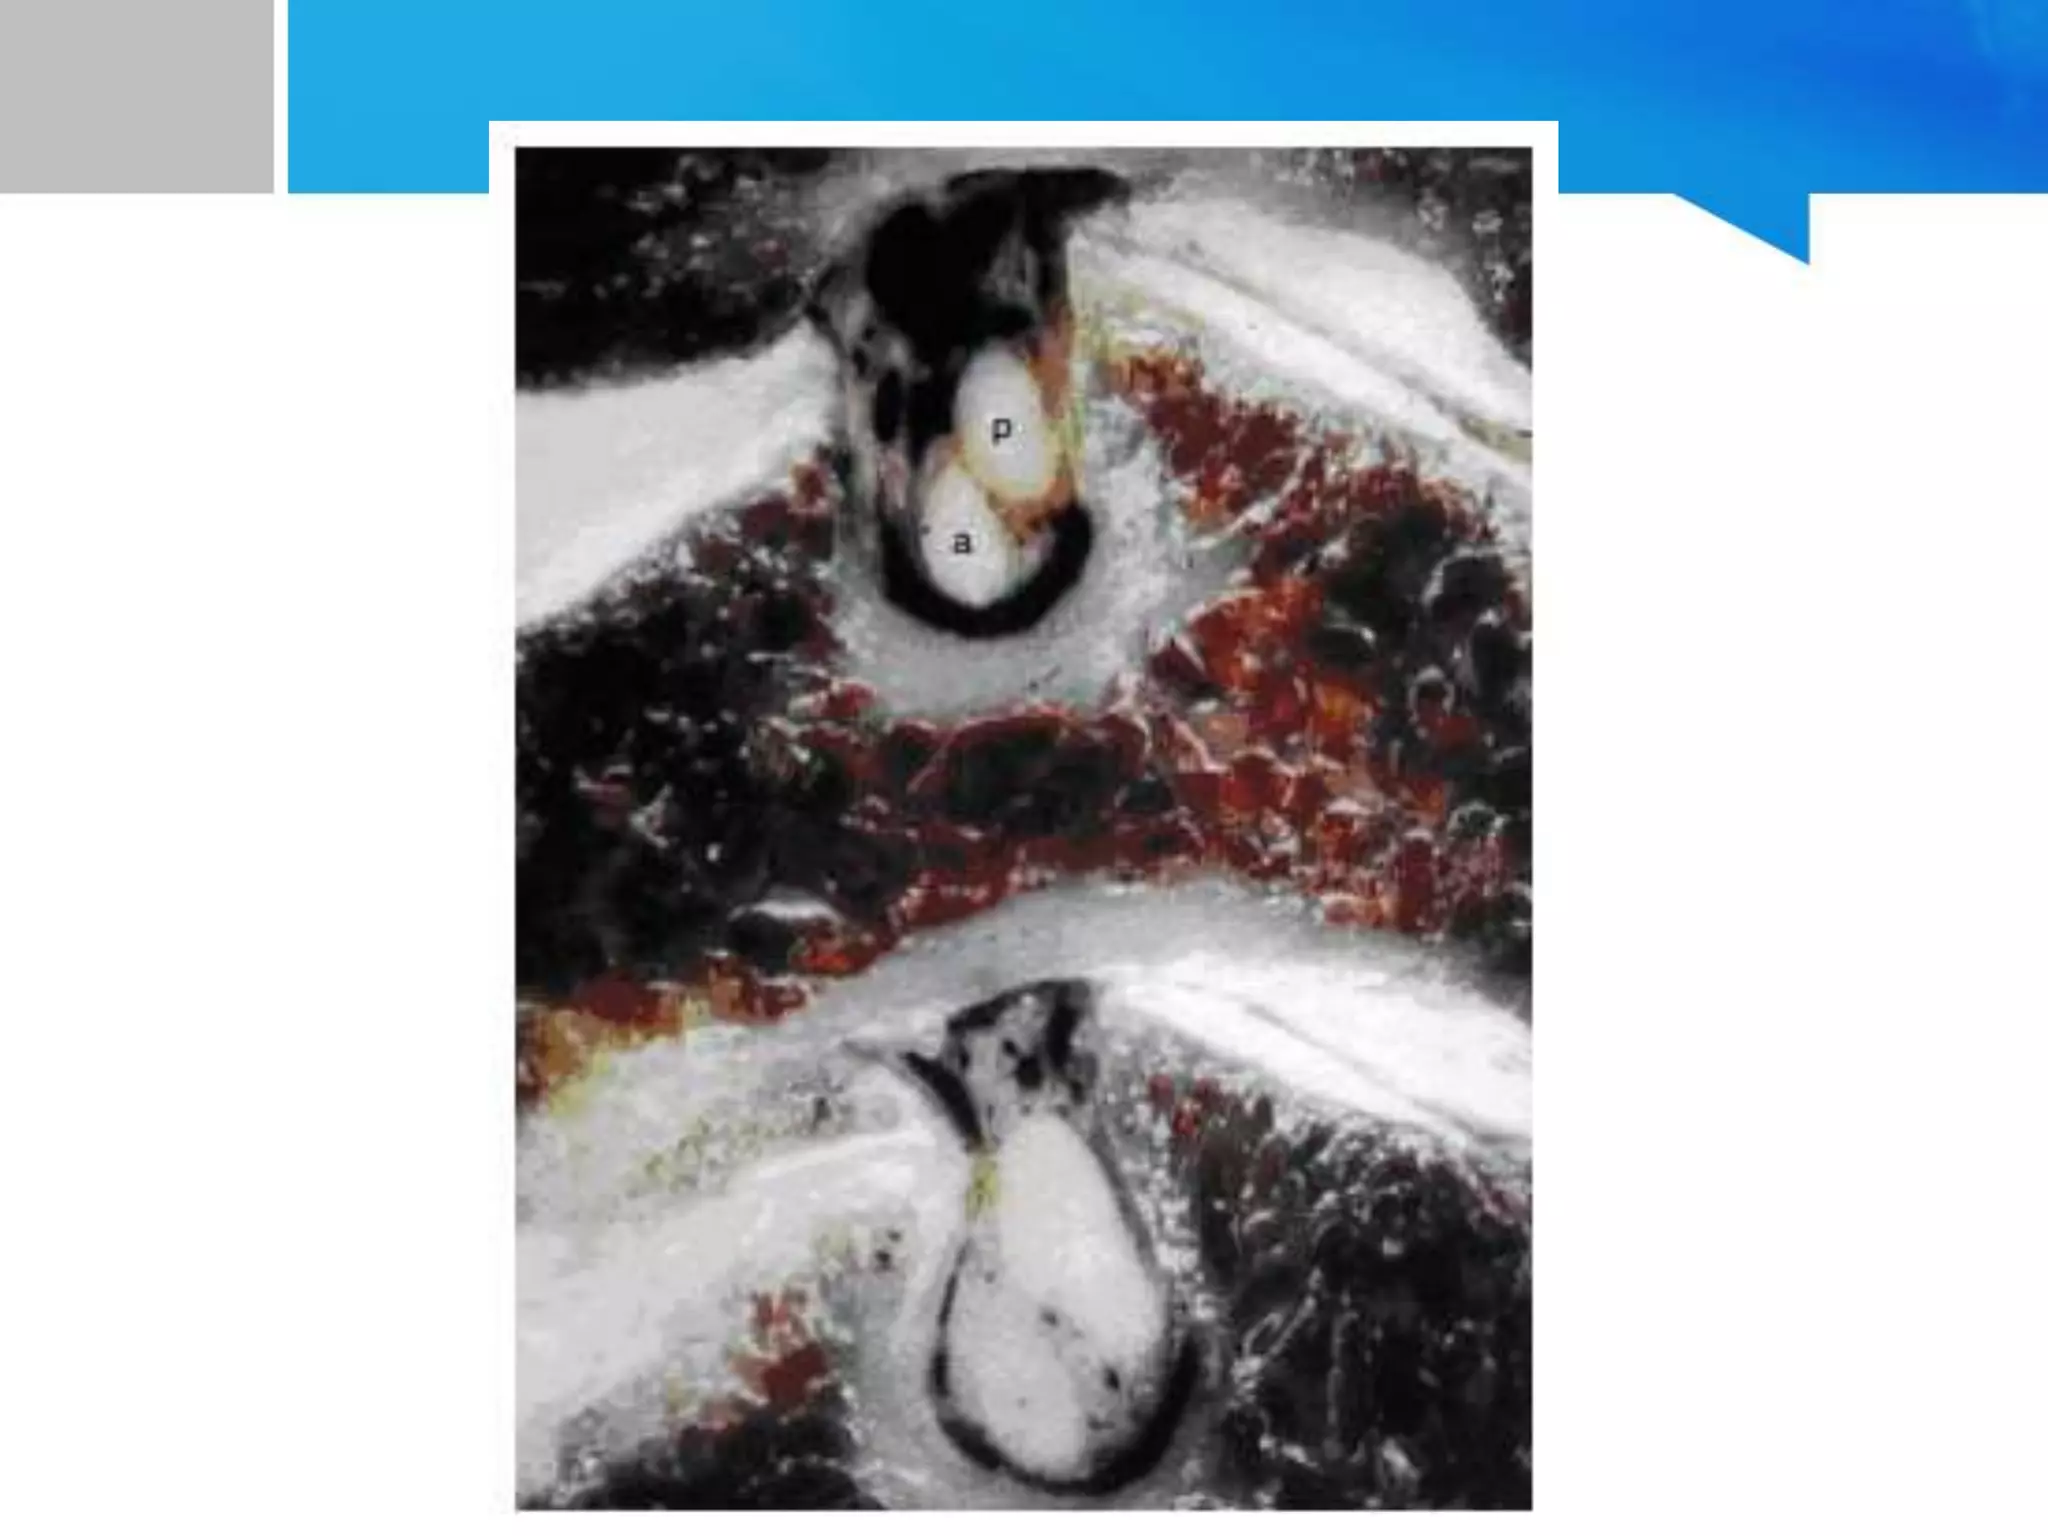

intervertebral foramen

• dorsal roots more rostrally hence comprression affects

disproportionately

• exiting root - oblique with a ventrolateral trajectory

• at origin

– bounded ventromedially by the UV joint

– laterally, the nerve root and DRG abut the VA

– UV hypertrophy and lateral discs cause radiculopathy

– UV hypertrophy also distorts the VA causing secondary

compression on the exiting root or DRG

• dorsolateral wall

– superior and inf articular processes, hence facet hypertrophy

triggers radiculopathy

– basis of Spurling's maneuver

• the roots lie more caudally, abutting the subjacent pedicle